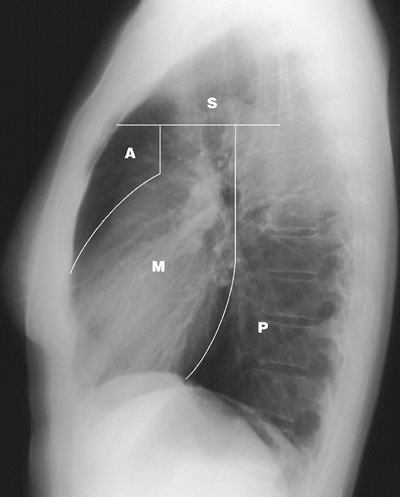

The mediastinum can be divided into compartments, and many classification systems have been devised to simplify the differential diagnosis when an abnormality is seen in one or more compartments. A system based on anatomic subdivisions (the superior, anterior, middle, and posterior mediastinal compartments) will be used in this chapter (Fig. 6-1). Approximately 60% of all mediastinal masses arise in the anterior mediastinum, 25% appear in the posterior mediastinum, and 15% occur in the middle mediastinum (1). When an abnormality is not isolated to one mediastinal compartment, as is often the case with large mediastinal masses, the list of diagnostic possibilities can be determined by localizing the abnormality to the mediastinal compartment serving as the "epicenter" of the abnormality or by considering all abnormalities that occur in the compartments involved. Associated radiologic findings can also help to narrow the list of diagnostic possibilities; these include deviation of the trachea (commonly seen with thyroid masses); presence of axillary, abdominal, and retroperitoneal adenopathy (suggesting the diagnosis of lymphoma); or posterior rib erosion or destruction (consistent with a posterior mediastinal mass, such as a neurogenic tumor).

FIGURE 6-1. Mediastinal compartments. Lateral chest radiograph shows the boundaries delineating the superior (S), anterior (A), middle (M), and posterior (P) mediastinal compartments.